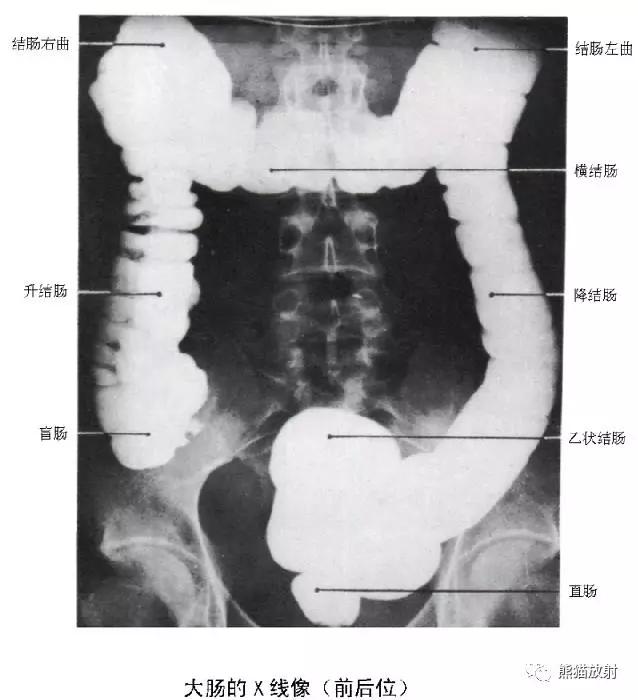

10 Colon 结肠

1 Splenic flexure of the colon 结肠脾曲,2 Hepatic flexure of the colon 结肠肝曲,3 Ascending colon 升结肠,4 Transverse colon 横结肠,5 Descending colon 降结肠,6 Haustra 结肠袋,7 Ileocecal valve 回盲瓣,8 Cecum 盲肠,9 Sigmoid colon 乙状结肠,10 Appendix 阑尾,11 Rectum 直肠